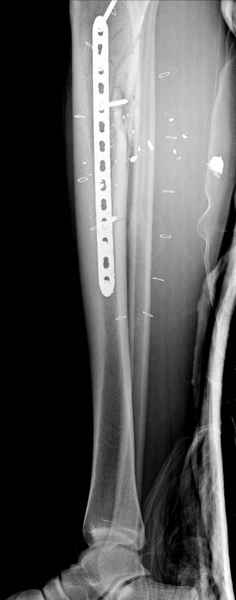

1 неполный перелом большеберцовой кости перкутанная пластина

2 перелом бедра